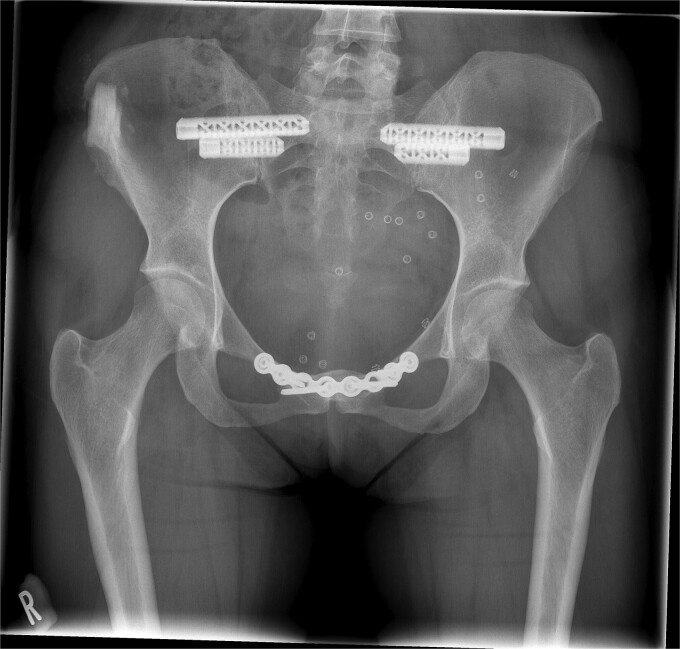

Introduction: Surgical treatment of pelvic girdle pain (PGP) involves arthrodesis of sacroiliac (SI) and pubic symphysis joints. Fusion of pubic symphysis involves the implantation of an autologous iliac crest tricortical graft harvested from the iliac crest. The objective was to assess the safety of a novel synthetic graft substitute (b.Bone) for iliac crest reconstruction and to evaluate the results of PGP surgical treatment.

Sources of data: Consecutive participants undergoing pelvic fusion and requiring iliac crest reconstruction were enrolled and followed-up for 12 months in a prospective first-in-human clinical investigation. Adverse events were documented, and health-related quality of life was evaluated using EuroQol-5D-5L questionnaire. Iliac crest defect healing was evaluated by the Modified Lane and Sandhu radiological scoring system. In addition, relevant published peer-reviewed scientific articles identified from PubMed.

Areas of agreement: The EQ-5D-5L scores improved steadily reaching the highest point at 365 days. By 365 days complete healing of the bone defect was observed.

Growing points: While there is lack of consensus on how to manage PGP, the present study shows improved outcomes at one year following surgery. The synthetic b.Bone scaffold is a safe option with good healing outcomes for iliac crest defect reconstruction.